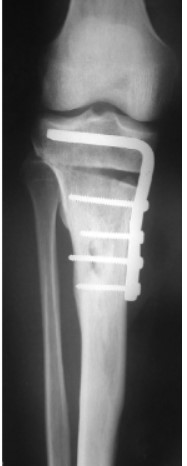

Galerija 1 Osnovne informacijeO namaDjelatnostiPreporuka za VasKako do nasPovoljna cijena ortopedskih pregledaGostovanje u emisiji Bez uputniceVažnost ultrazvučnog pregleda dječjih kukovaGalerija 1Galerija 2Galerija 3.1.Galerija 3.2.Galerija 4Galerija 5Cerebralna Paraliza i Ortopedske IntervencijeKako se pripremiti za manji operacijski zahvatSavjeti ortopeda za najčešće sportske ozljede i njihova prevencijaKralježnica: Važnost ranog prepoznavanja deformiteta i bolesti kralježniceKoljenski zglob: Razlozi brzog trošenja hrskavice, čestog ozljeđivanja i mogućnosti liječenjaPonude i popustiKarta - kako do nas?KomentariKontakt Galerija 1 Objavljeno: 18.9.2023. 15:20